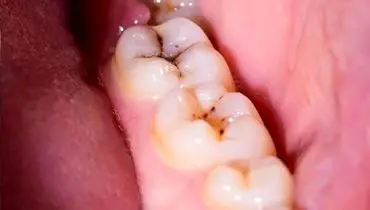

پوسیدگی دندان با وجود مسواک زدن همچنان شایع است و پیشگیری مؤثر، نیازمند رویکردی جامع و شخصیسازیشده به سلامت دهان است.

کرم خوردگی دندان : اکثر افراد تصور می کنند که دندان کرم خورده را دیگر نمی توان درمان کرد. این در حالی است که تحقیقات…

پوسیدگی دندان همیشه به پرکردن ختم نمیشود؛ با تغییر سبک زندگی میتوان جلوی آن را گرفت